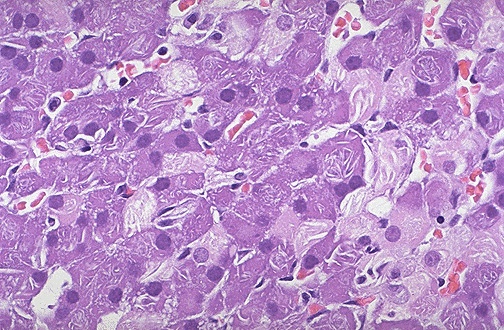

| Metabolic disorders can sometimes be diagnosed prenatally from fetal cells grown in culture and obtained by amniocentesis. Seen here are peculiar clear clefts in adrenal cortical cells which are inclusions of long chain fatty acids in a case of adrenoleukodystrophy which was diagnosed antenatally. |